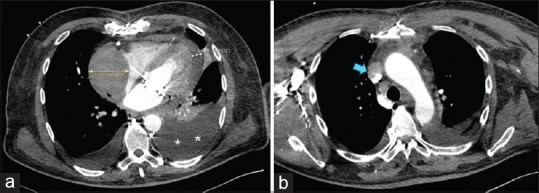

Abstract: Although most superior vena cava (SVC) syndromes are due to intrathoracic malignancies, some are iatrogenic, such as those following the intravenous implantation of pacemaker wires. To date, the occurrence of this syndrome after epicardial pacemaker removal has not been described. The initial auricular laceration after removal can be complicated by the administration of anticoagulant and antiplatelet drugs, forming a hematoma that compresses the SVC cranially. Therefore, standardized practice may be necessary in these patients to address anticoagulant and antiplatelet therapy, perform serial echocardiography, and pay attention to underlying symptoms, which may be insidious and delayed.